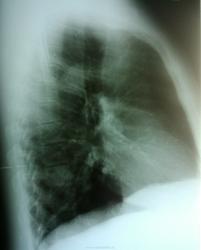

Дообследование.

Согласна с коллегами. Справа в S 10 периферическое образование, учитывая рост, более вероятно  C-r.  Cлева в среднем поле   воздушная киста

... Cлева в среднем поле - воздушная киста

Если она там, тогда не одна.)

Я одну вижу. Добавите?

периферический рак справа + кисты в левом легком  в средних и нижних отделах

Господи! Какой ретроспективный анализ? Она-оно (зло) растет себе и растет, кстати, на фоне этих кист в обоих легких ( Nobody, Вам-особенный респект!)